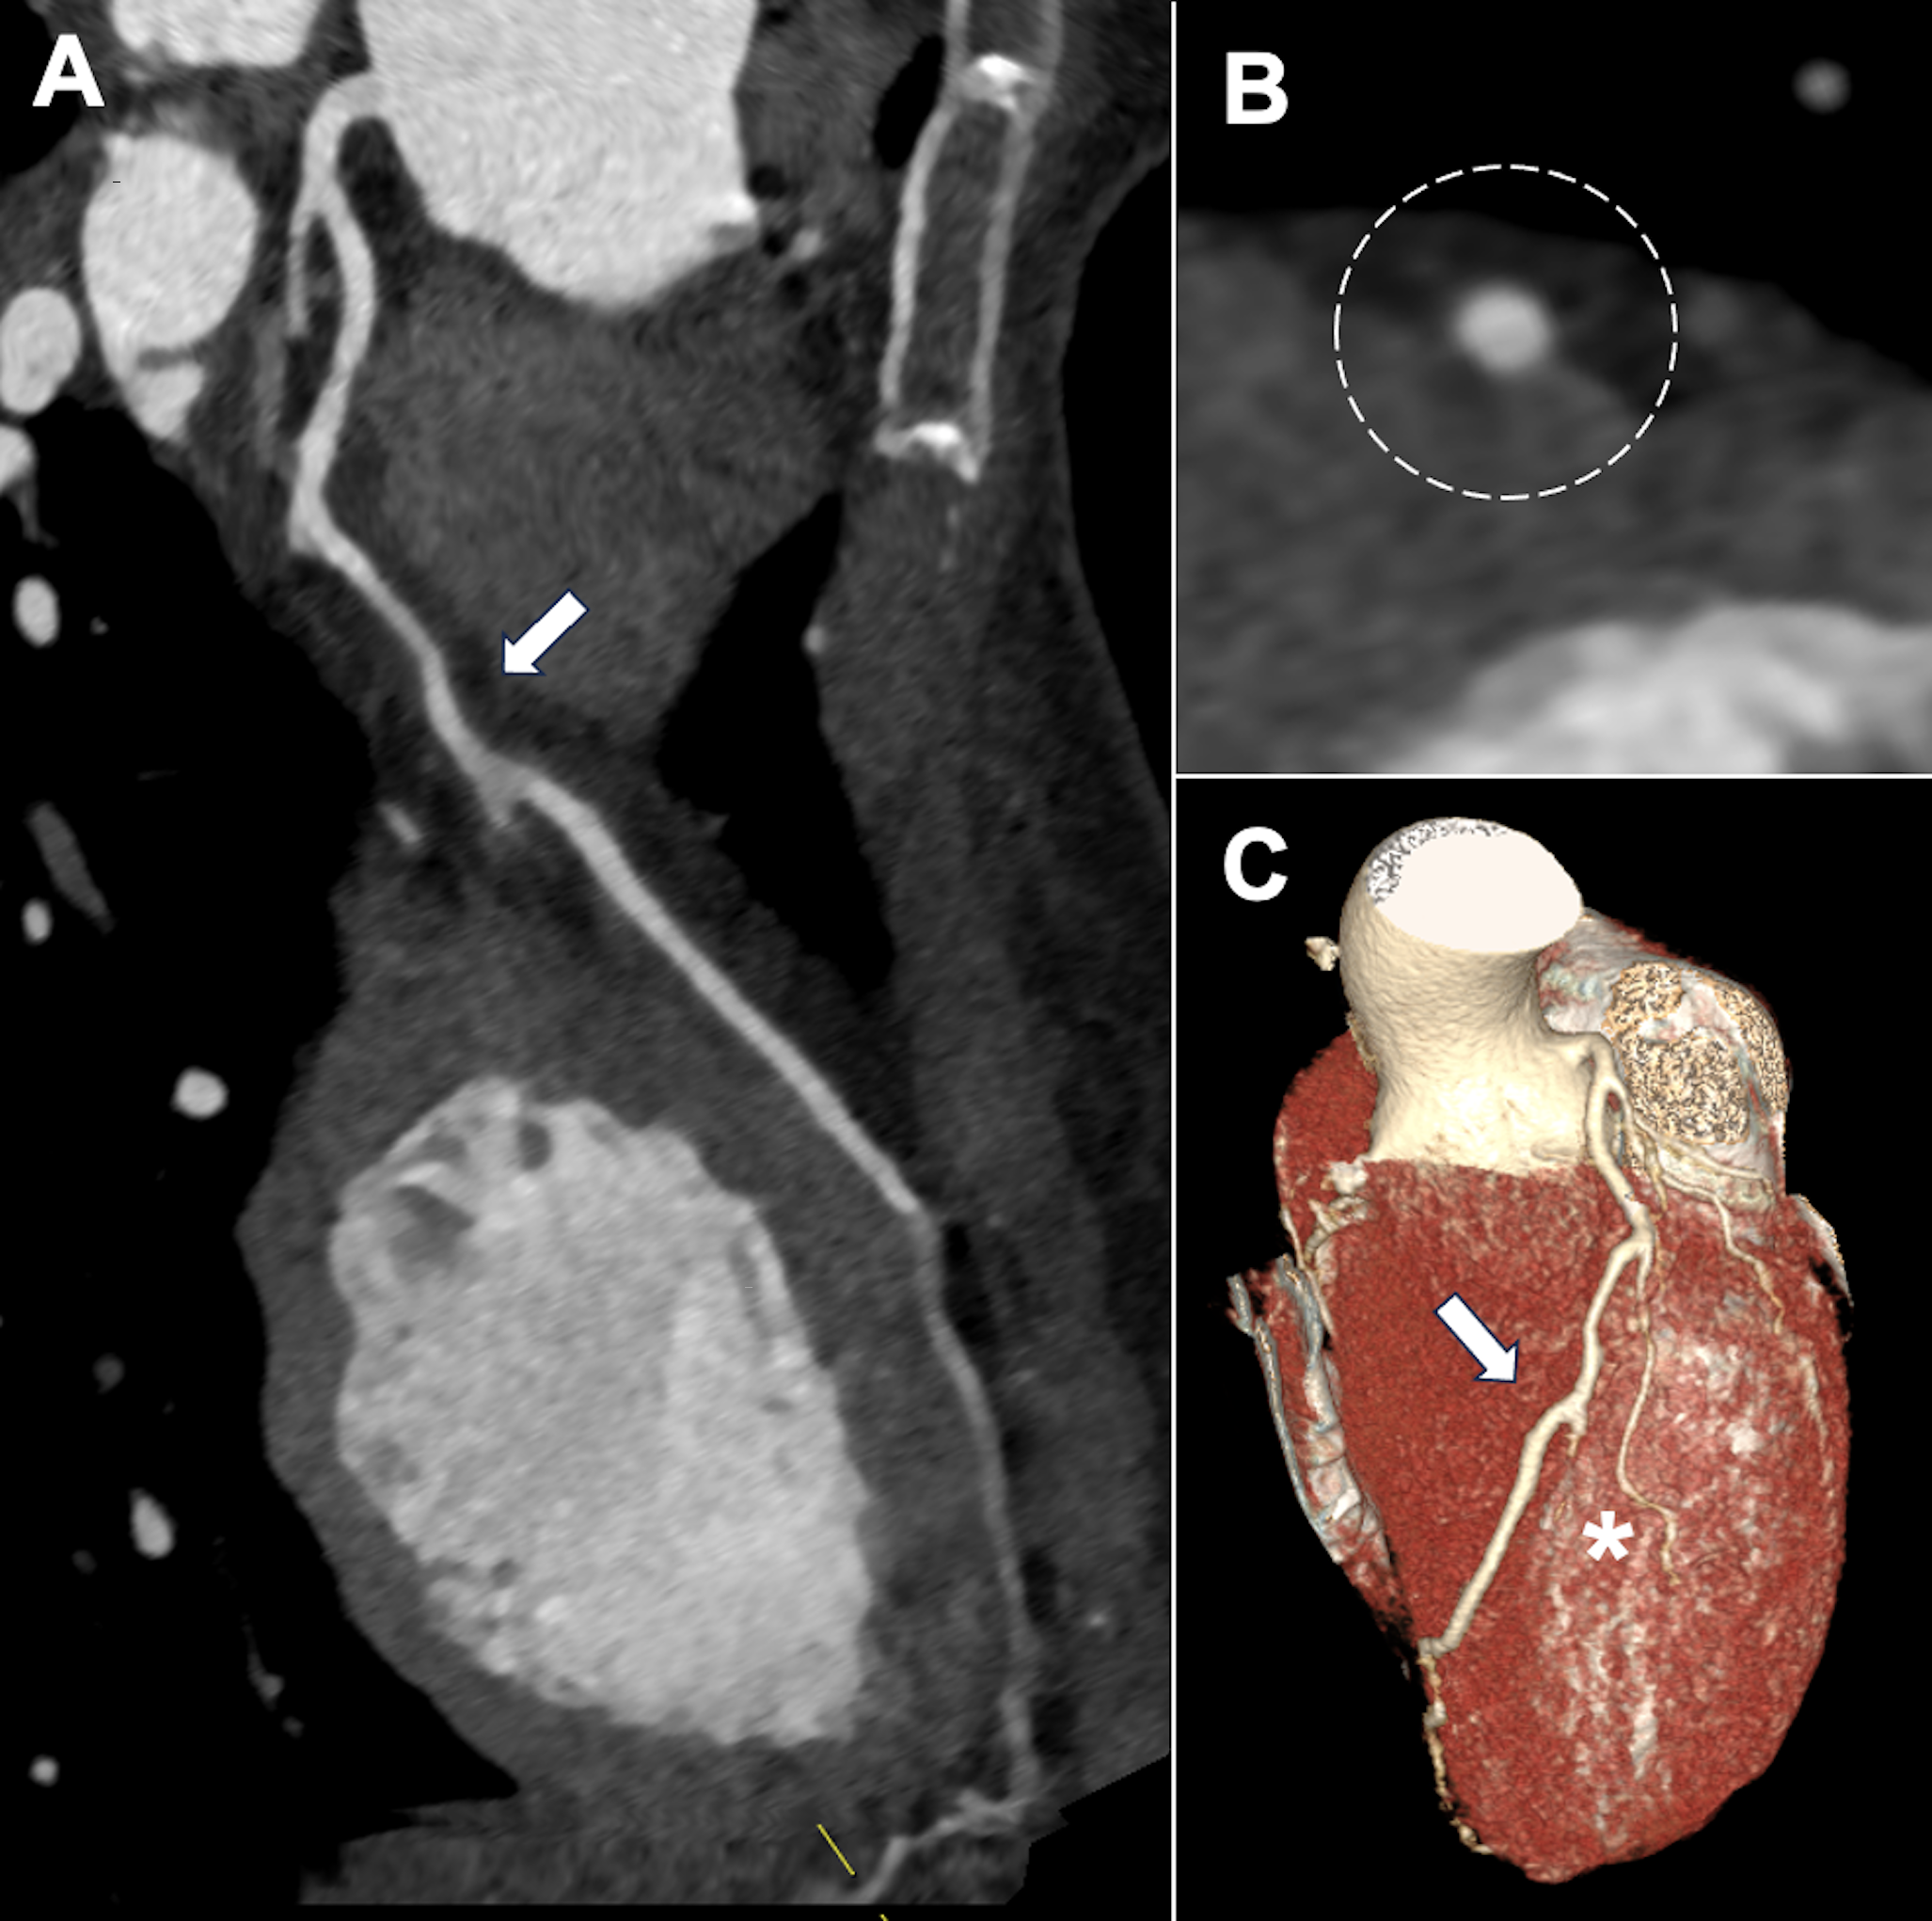

A 37-year-old woman with no prior medical history was admitted with a non-ST-segment elevation myocardial infarction. Despite initial medical therapy, she developed refractory chest pain, T-wave inversion in the precordial leads, and anterior wall akinesia on echocardiography. Emergent coronary angiography revealed a long, smooth, and diffuse narrowing of the mid-left anterior descending artery (LAD), characteristic of type 2 spontaneous coronary artery dissection (SCAD), along with features of type 3 SCAD in a small second diagonal branch (Figure 1A).

Given ongoing ischemia and hemodynamic stability, a percutaneous coronary intervention was performed with a deliberate stent-avoidance strategy. A cutting balloon was used to fenestrate the intramural hematoma and decompress the false lumen (Figure 1B), achieving full restoration of LAD flow and complete resolution of symptoms (Figure 1C). No stents were implanted. Coronary computed tomography angiography before discharge confirmed a patent LAD without intramural hematoma or atherosclerosis (Figure 2).